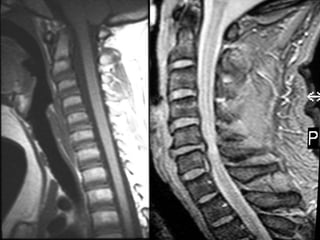

Coluna Cervical Coluna vertebral Tomografia axial Ressonância Magnética T2

• #9 Aspectos a TC e RM cervical

• #10 RM cervical Sagital